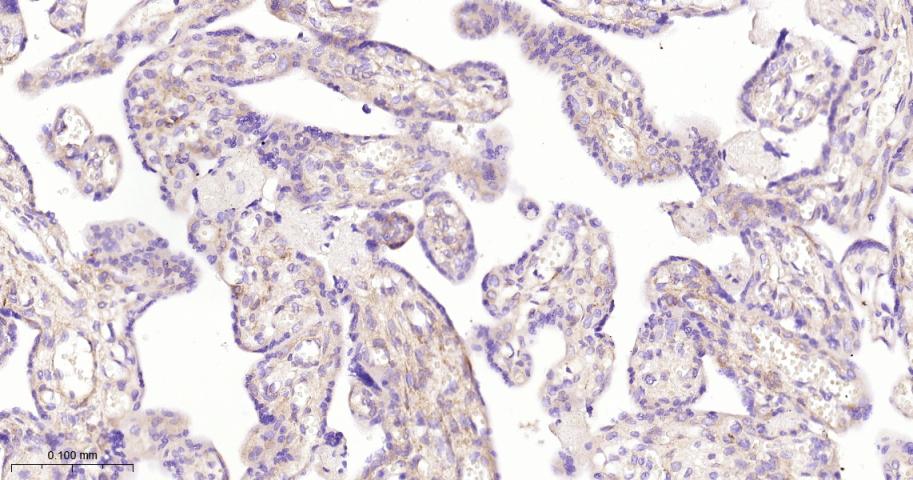

Paraformaldehyde-fixed, paraffin embedded Human Placenta; Antigen retrieval by boiling in sodium citrate buffer (pH6.0) for 15 min; The section was incubated with SOD3 Monoclonal Antibody, Unconjugated (bsm-61605R) at 1:200 overnight at 4°C, followed by conjugation to the bs-0295G-HRP and DAB (C-0010) staining.